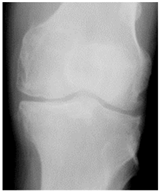

In the local dataset, we have selected 60 adult patient files of men and women with knee disorders who were radiographically examined at the Radiology Department of the El Kelaa des Sraghna Provincial Hospital. Each file consists of one or more knee radiographs in Dicom format as presented in Figure 7. The images were acquired using a standard ITALRAY radiology table. After analysis, 30 images with implants and non-posterior-anterior examination views were excluded and 30 left and right Dicom knees were retained to validate this work. To make the validation local dataset, the ROI was selected manually as illustrated in Figure 8. Then, each patient’s file was presented to a rheumatologist with PNG images. In case of disagreement between our diagnostic system and the rheumatologist, a radiologist was consulted for arbitration to make the final decision.

Figure 7.

Example of knee X-ray images collected and filtered from patients with knee symptoms.